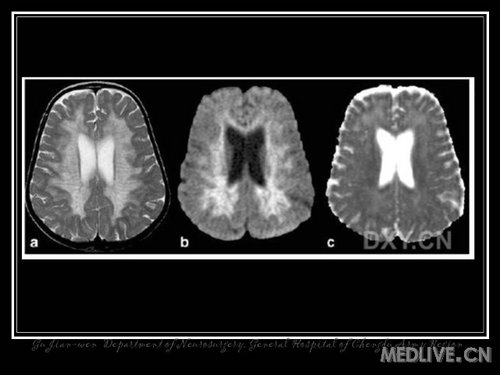

可怕的脑渐死-脑白质变性类疾病(六)